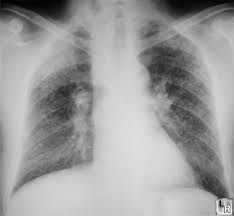

Black lung disease can be diagnosed by checking a patient's history for exposure to coal dust, followed by a chest x-ray to discover if the characteristicspots in the lungs caused by coal dust are present. A pulmonary function test may aid in diagnosis.

X rays can detect black lung disease before it causes any symptoms. If exposure to the dust is stopped at that point, progression of the disease may be prevented.

• Chest x rays will usually show small round opaque areas in chronic silicosis. The round areas are larger in complicated and accelerated silicosis.